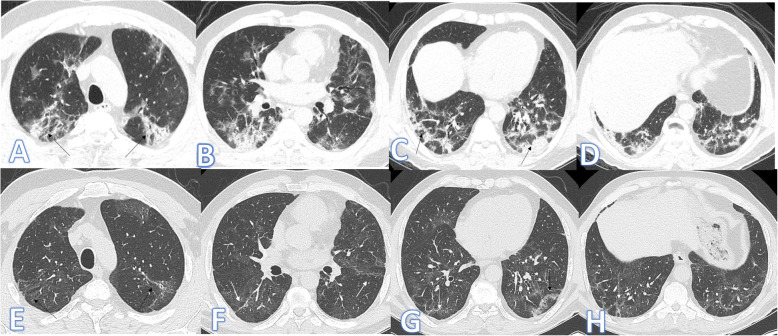

Fig. 2.

Fifty-nine-year-old male: he has DM; peak CT severity score 10; consolidation/crazy-paving score 8. No ICU admission; laboratory results show lymphopenia, high CRP, d-dimer, and serum ferritin. Steroid was given; length of stay during hospitalization is 10 days. Peak CT (a–d) shows bilateral peripheral consolidation patches mainly in the lower lobes (arrows). Follow-up CT 2 months after discharge (e–h) shows residual fibrosis with parenchymal bands, coarse reticular pattern (arrows), and atoll sign (black arrow in g).